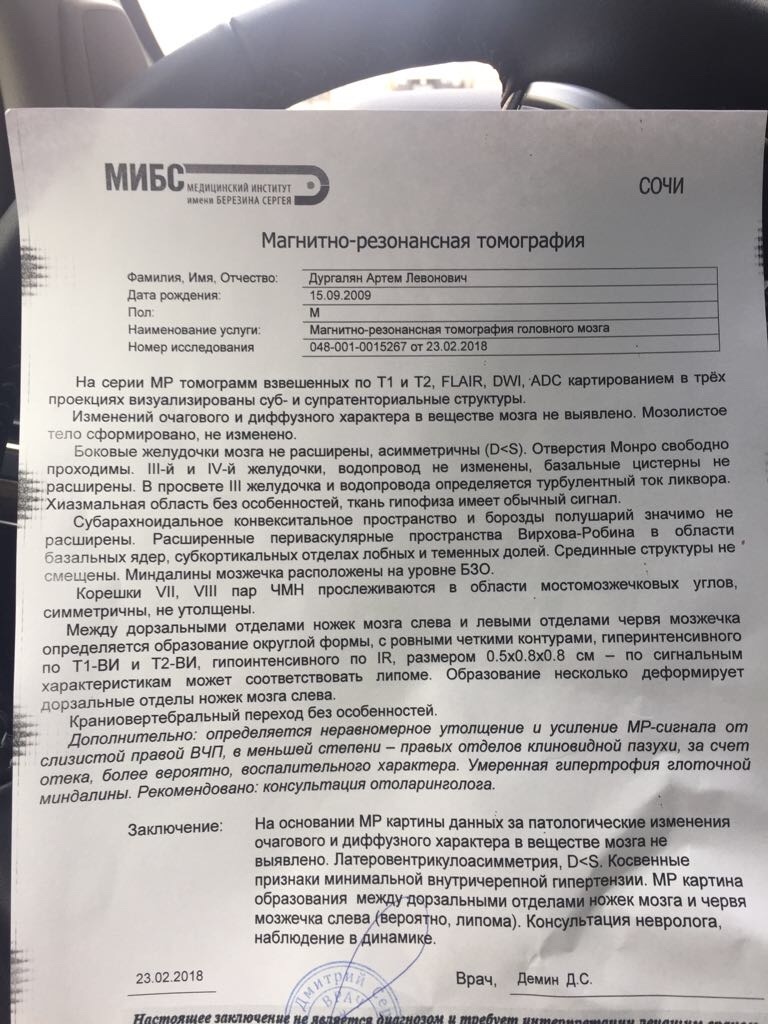

МРТ головного мозга: Расшифровка снимков и Интерпретация

Раздел: Визуальные уроки